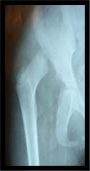

Conducted CME’s, OPD’s & Surgeries at various Hospitals in Ethiopia |

Conducted CME's, OPD's & Surgeries at various Hospitals in Ethiopia-2011